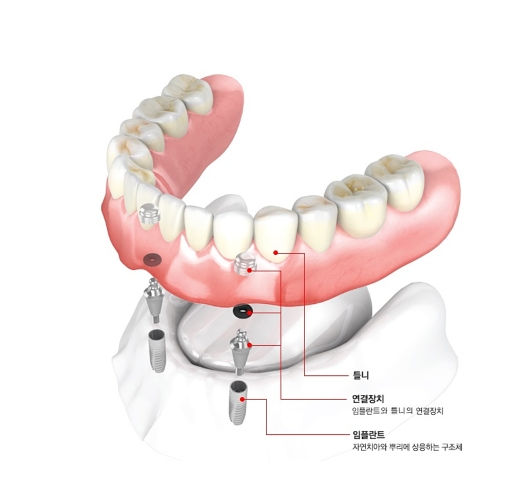

2. 임플란트를 이용한 틀니입니다.

하악치아에 뼈가 풍부한 양측 신경과 사이에 2개에서 4개의 임플란틀를 심어서 임플란트 상단에 자석이나 혹은 똑딱이 단추를 연결하여서 틀니를 유지해 주는 방법입니다. 요즘도 많이 하는 치료 방법이며 보통 아래턱에는 2개의 임플란트를 이용하여 많이 진행합니다.